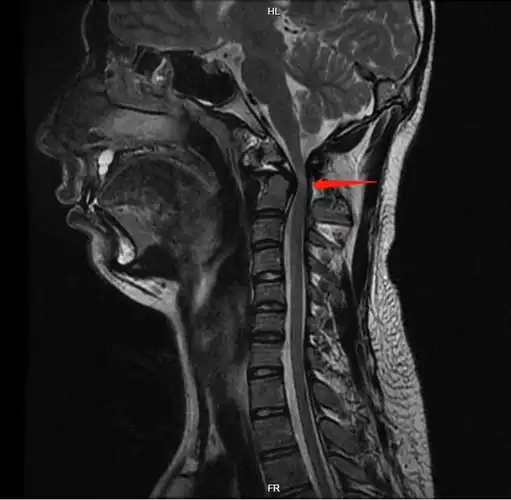

颈椎间盘突出征核磁共振矢状位(mri)

脊柱mri解剖图片